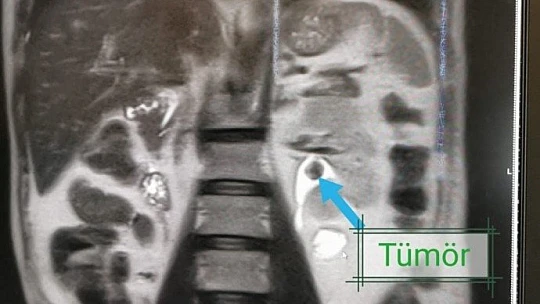

Yapılan tetkikler sonucunda hastanın nadir uygulanan yöntemle sağlığına kavuştuğunu ifade eden Op. Dr. Serhat Yentür, "Hastamıza kontrastsız emar (MR) çektik. MR’de sol böbreğin ana çıkış alanında 3 santimetrelik bir lezyon görüldü. Yani böbrek içinde bir tümör vardı ve onun temizlenmesi lazımdı. Normal şartlarda iki böbreği sağlıklı olan insanda bu böbreği alırız. Ama bu hastamız, tek böbrekli olduğu için böbreği aldığımız zaman hasta direkt diyalize bağlı kalacaktı. Hastamıza bir şans tanıdık ve dünyada çok nadir yapılan bir yöntemi uygulamaya karar verdik. Bu yöntem böbreğe yandan girilerek orada bir tüp oluşturup böbreğin içine perkütan yöntemi ile girilmesinin ardından tümörü tur aletleriyle kazıma işlemiydi. Bu yöntem ve teknikle ameliyat yaptık ve çok başarılı oldu. Hastamız da takiplerine geldi ve gayet iyi. Kreatinlerinde de artma olmadı. Böbreği koruyarak bu ameliyatı başarılı bir şekilde yapmış olduk. Şimdiye kadar dünyada 83 tane bununla ilgili bildirilmiş vaka var, bizim hastamız 84’üncü oldu. Bunu Elazığ’da Medical Park Hastanesi’nde yaptık ve hastamız gayet iyi durumda. Ameliyattan 3 gün sonra hastamızı ayakta taburcu ederek evine gönderdik. Ameliyattan sonra tekrar orada tümör çıkmaması için böbrekten girdiğimiz alandan ilaç uygulaması yaptık. Her şey istediğimiz gibi gitti. Hastamızın tetkikleri temiz, bundan sonra da kontrollerine devam edeceğiz” diye konuştu.